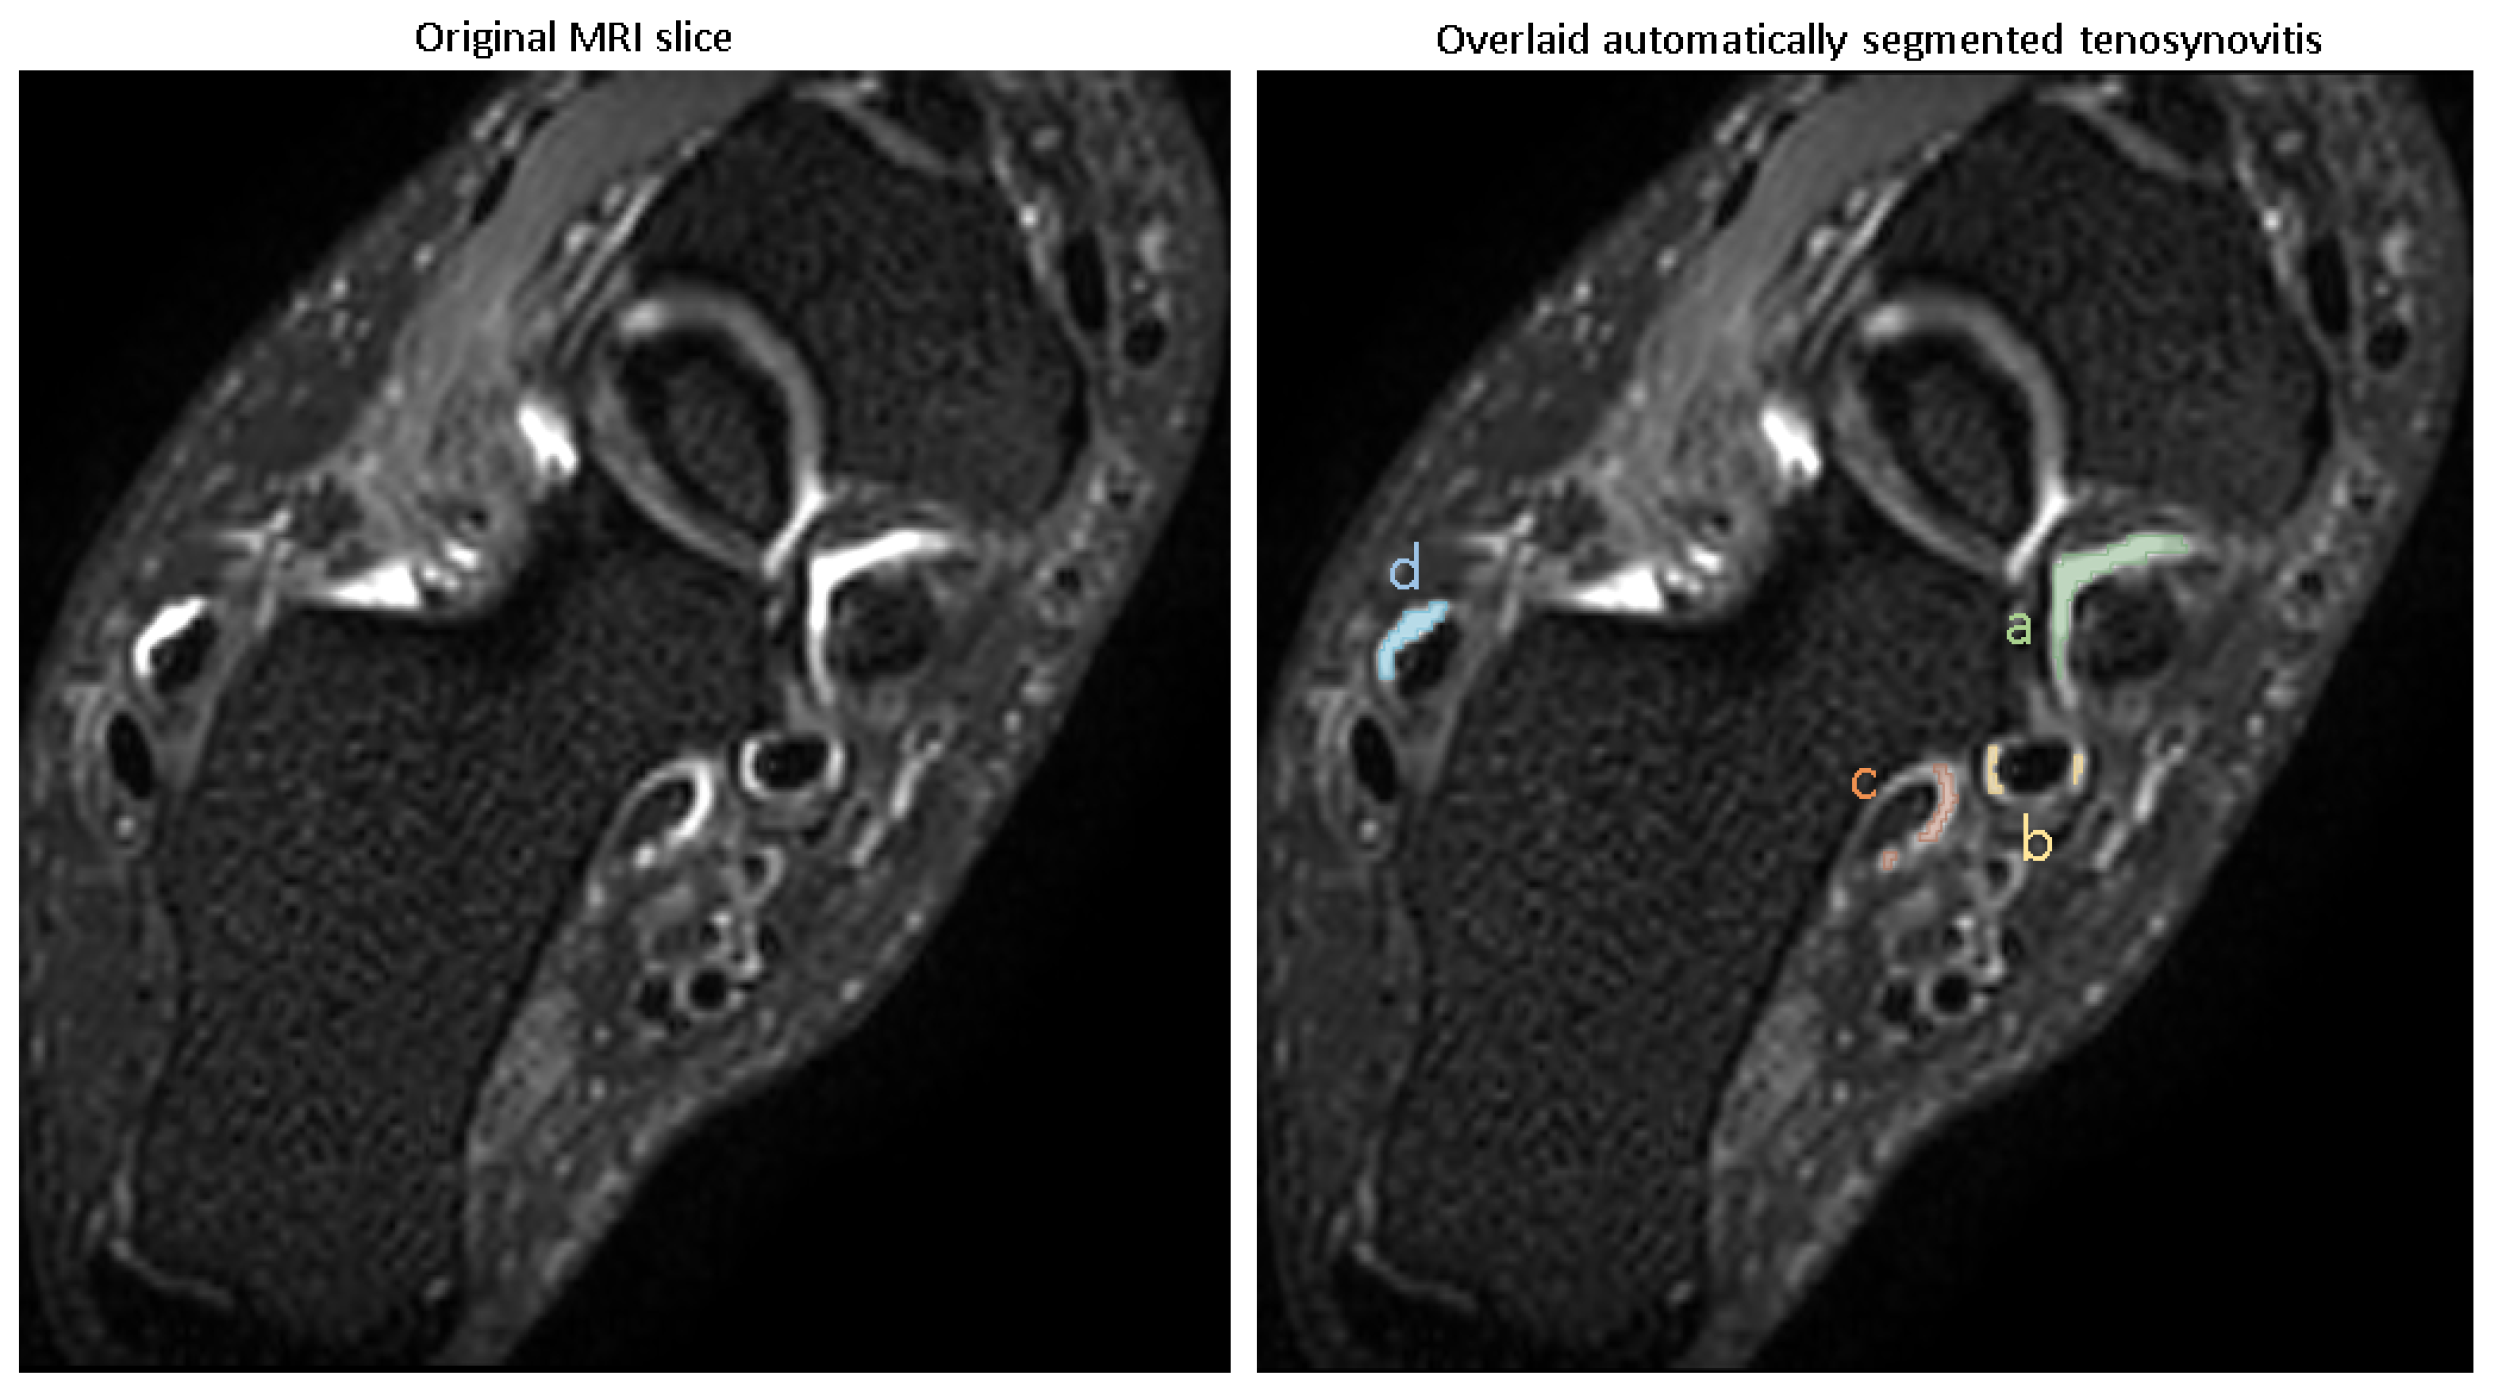

In order to automate the segmentation of tenosynovitis pathologies and validating this process, a dataset of ground truth tenosynovitis segmentation was required. Tenosynovitis ground truth segmentation as shown in Figure 2 was performed in a human–machine workflow to speed up the generation of dataset and to increase the consistency across readers. In the human–machine workflow, a radiologist (WF) supervised an image processing pipeline that generates initial pathology segmentations. These segmentations were then corrected by an MD researcher with 5 years of experience in orthopedics imaging (LC) and approved by radiologist (WF).

The details of the human–machine workflow are as follows: In the first step, as foot tenosynovitis pathologies are around any of 4 tendon regions, these 4 structures were segmented. As peroneal tenosynovitis occurs around both peroneal longus and peroneal brevis tendons, both these structures were segmented. This step is shown in Figure 2a. An MD researcher with 5 years of experience in orthopedics imaging (LC) performed manual segmentations of tendons on a set of 50 MRIs utilizing the 3D Slicer software, version 5.0.1. All 50 tendon segmentations were then reviewed by one musculoskeletal radiologist (WF).

In step 2, ROIs around the segmented tendons were automatically extracted, as depicted in Figure 2b.

In step 3, fuzzy c-means clustering was applied to the image voxels with the assumption of two clusters (brighter/darker voxels). Then, voxel intensities surpassing the higher cluster center value inside ROI underwent a threshold optimization for probability of those voxels belonging to the cluster. The illustrative result of this clustering method is encapsulated in Figure 2c. The threshold values that yielded the highest correlation of pathology volume with the radiologists’ semi-quantitative pathology scores were taken for further consideration by musculoskeletal radiologist (WF). The radiologist reviewed potential threshold levels on a selection of 10 MRIs from training set, representing various degrees of severity, to identify a probability threshold that most accurately captures the presence of pathology. We applied the same threshold across all four tendon regions, as the signal characteristics of tenosynovitis in these ROIs were visually consistent across images acquired with the same MRI protocol. Importantly, all resulting segmentations were reviewed and, if needed, corrected by an expert reader, ensuring validity regardless of the initial threshold. This ensured that the final annotations used for model training were consistent and accurate. While more advanced, adaptive thresholding techniques may improve automation further, our fixed-threshold approach provided sufficient accuracy for the purposes of this feasibility study.

In step 4, using the chosen threshold value in previous step, inflammatory voxels were automatically segmented and retained if situated within the disease-specific ROI from step 2 or emanated from within this defined area. This is shown in Figure 2d.

Figure 2. Human–machine workflow of creating ground truth pathology segmentation dataset. (ad): (a): tendons segmented (colors), (b): ROIs around tendons defined (green), (c): clustering highlights regions (lighter regions), (d): highlighted regions inside ROIs selected (red).

Figure 4. Example image overlaid with automatic segmentation of 4 tenosynovitis pathologies. (a) Tibialis posterior tenosynovitis (score: 3), (b) flexor digitorum tenosynovitis (score: 1), (c) flexor halluces longus tenosynovitis (score: 1), (d) peroneal longus/brevis tenosynovitis (score: 1).